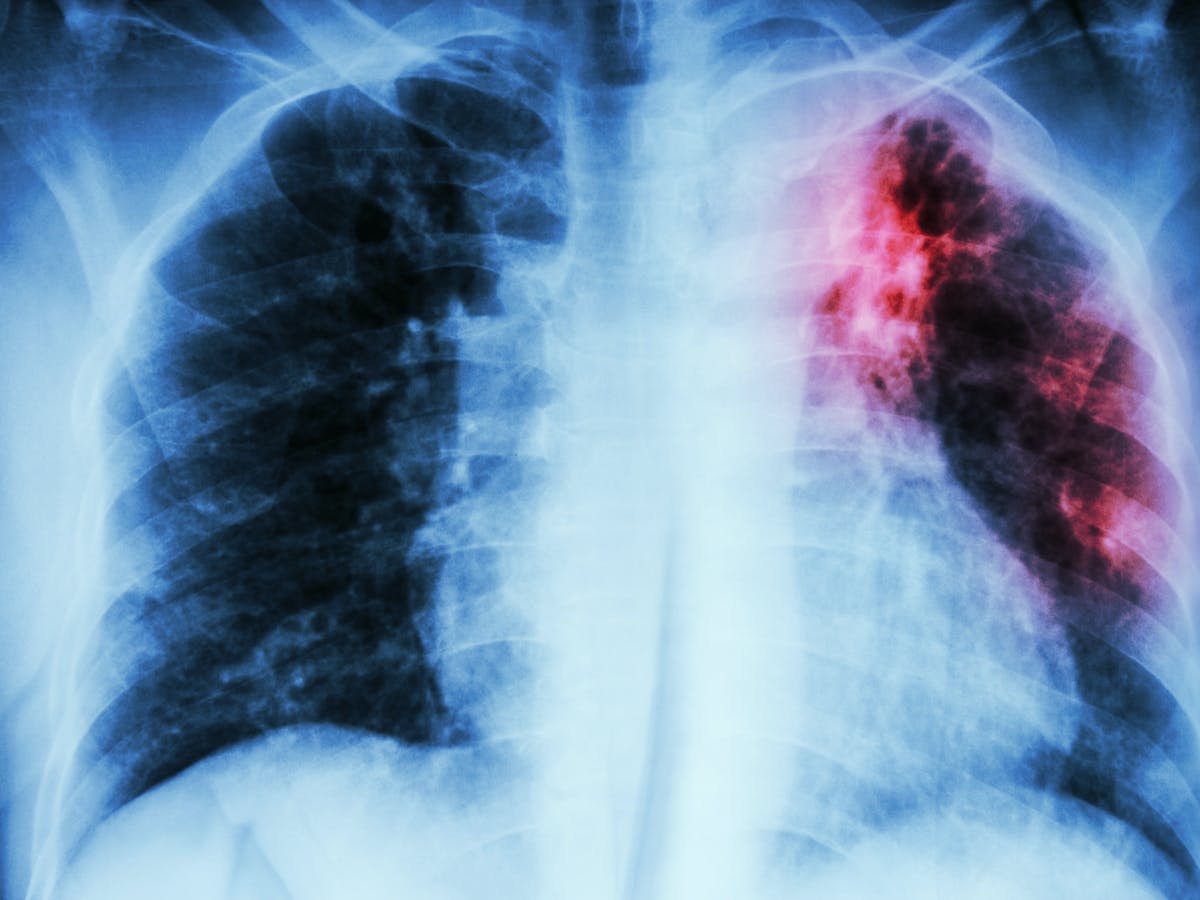

L’Organització Mundial de la Salut celebra aquest divendres el Dia mundial de la tuberculosi amb el lema “Sí podem posar fi a la tuberculosi”. El ministeri de Salut explica que durant el 2022 a través del Programa de prevenció i control va analitzant quatre sospites de la malaltia que s’han acabat confirmant. D’aquests, 1 correspon a un resident al país i 3 es van identificar al Servei d’Immigració. S’han detectat en homes d’entre 35 i 54 anys, així com s’ha fet un seguiment a sis contactes, dels quals 5 han estat dels casos detectats al Principat i un d’un cas d’Espanya amb una mitjana d’edat de 36 anys. S’han fet 11 proves de la tuberculina als contactes i en un cas ha donat positiu. Així mateix, s’ha fet una radiografia de tòrax.

La taxa d’incidència a Andorra anual es situa en 1,22 casos per cada 100.000 habitants. Si ens fixem en els darrers 25 anys, Salut va analitzar 218 sospites, de les quals 193 es van confirmar posteriorment. Concretament, 146 dels afectats eren residents al país i la taxa d’incidència en el darrer quinquenni és de 2,8, una dada és la segona més baixa dels darrers vint anys.